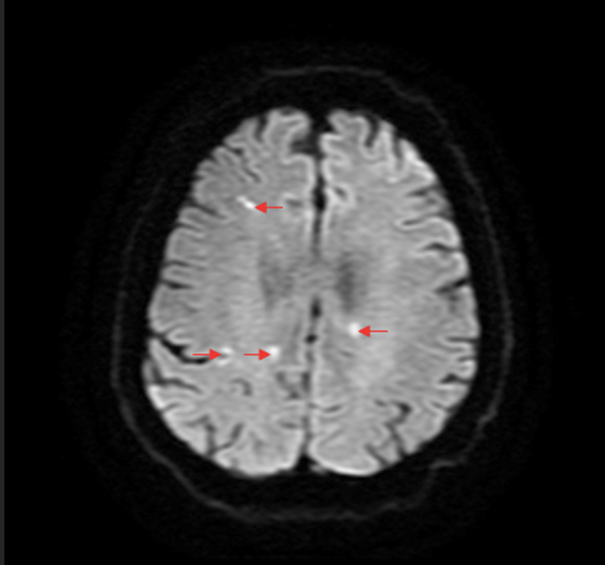

A Magnetic Resonance Imaging (MRI) scan of the brain was performed which demonstrated infarcts in both cerebral hemispheres (Figure 1). Cardiac telemetry for one week during his hospital stay did not demonstrate atrial fibrillation or other emboligenic arrythmias. Venous ultrasounds of bilateral upper limbs did not show any evidence of venous thrombosis. An acquired thrombophilia screen performed was negative. The patient underwent a transthoracic echocardiogram (TTE) followed by a transesophageal echocardiogram (TEE) which showed normal cardiac chamber sizes and normal coronary sinus appearance (Figure 2). There was no evidence of inter-atrial defects, patent ductus arteriosus or valvular abnormalities. No thrombus was visualized in the left atrium (LA) or its appendage. There was no evidence of atherosclerotic disease in the thoracic aorta.

Figure 1: Magnetic resonance imaging of the brain-diffusion weighted image: Multiple hyperintense signals (arrows) in both cerebral hemispheres.